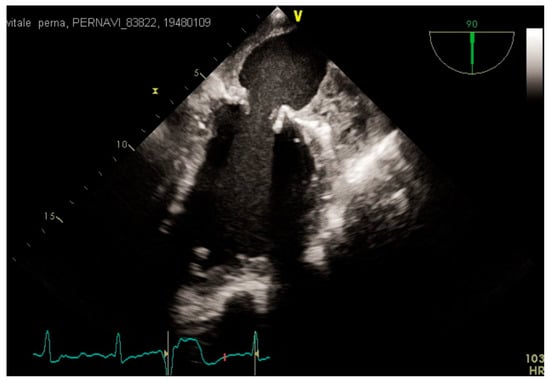

3.2. Transesophageal Echocardiography and Intracardiac Echocardiography